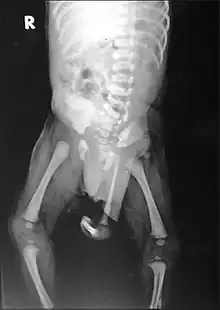

Radiograph of a human child with polymelia

Polymelia is a birth defect in which an affected individual has more than the usual number of limbs. It is a type of dysmelia. In humans and most land-dwelling vertebrates, this means having five or more limbs. The extra limb is most commonly shrunken and/or deformed. The term is from Greek πολυ- "many", μέλεα "limbs".